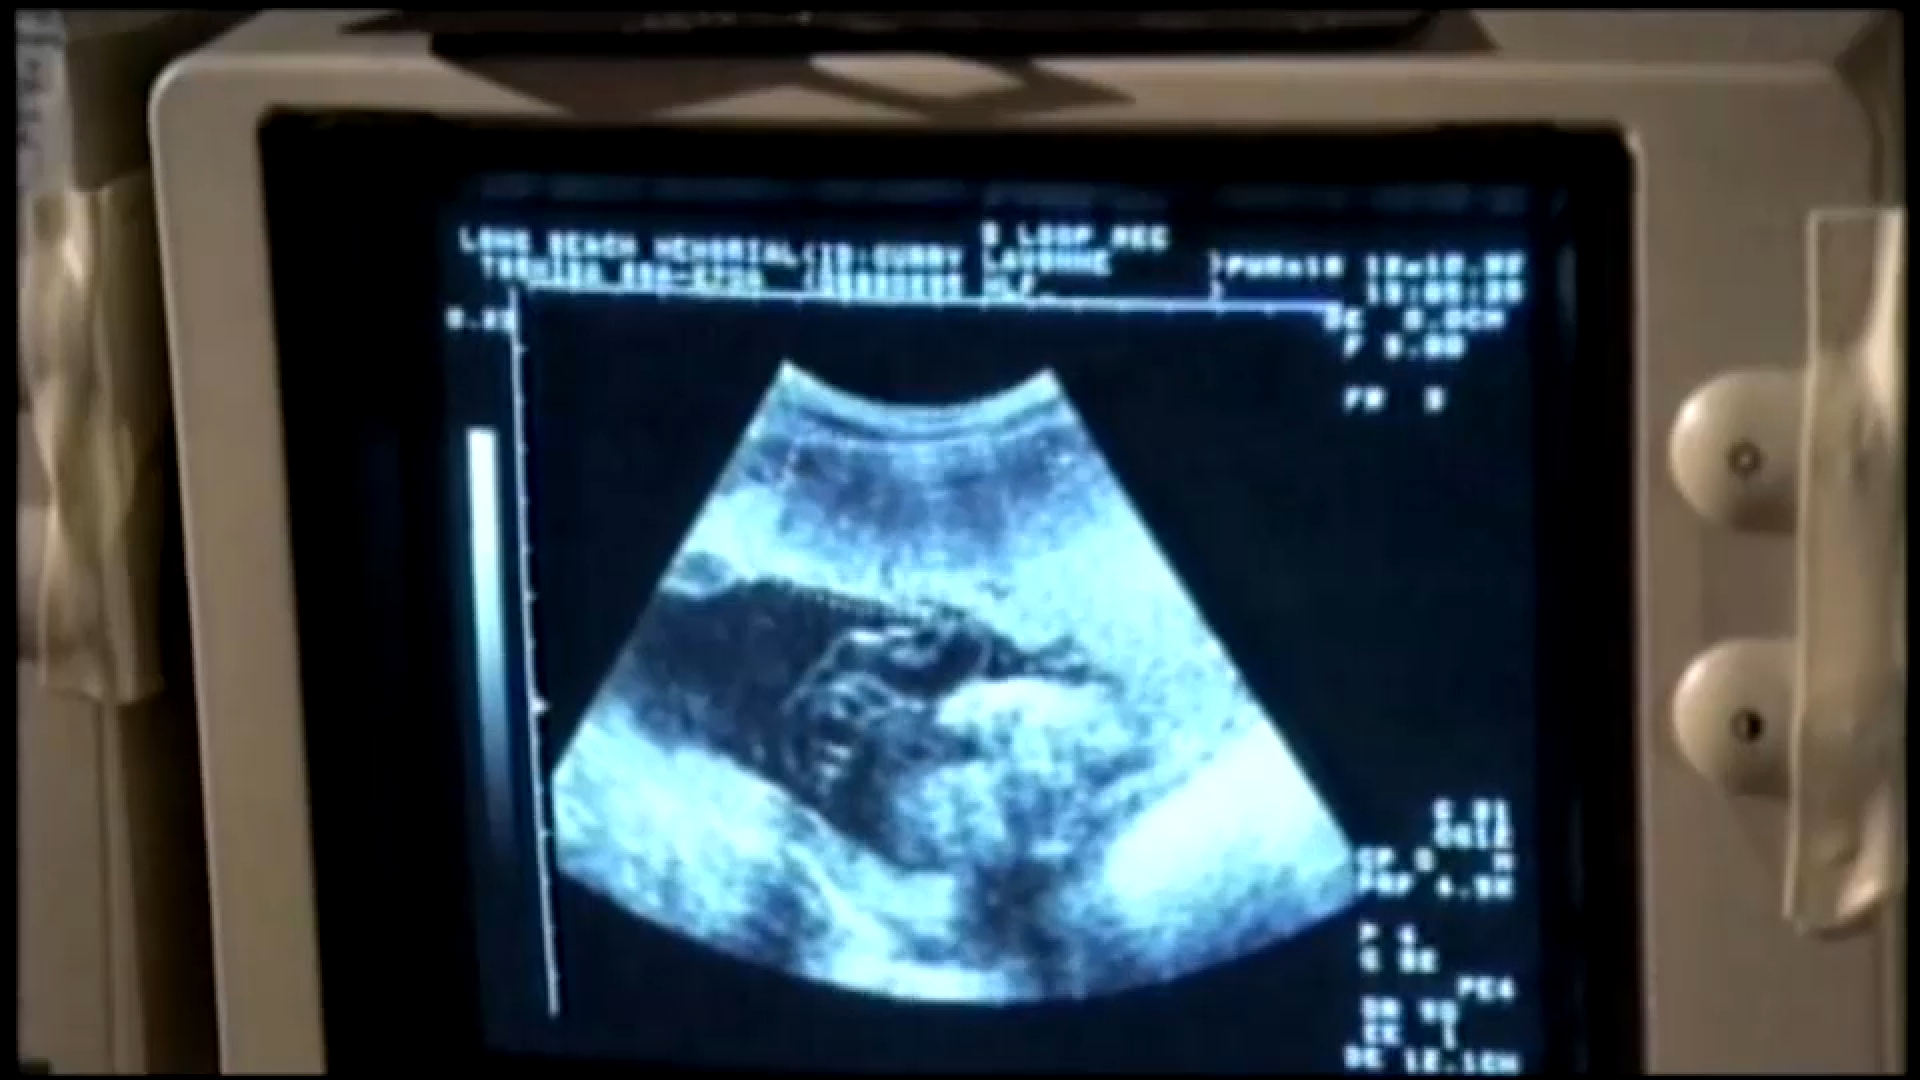

Through the analysis of patient ultrasounds, the team creates digital twins of patients that allow them to understand better the causes of preterm birth. “One of the biggest problems is just identifying patients who could be at high risk for mechanical failure of their cervix,” Myers noted.